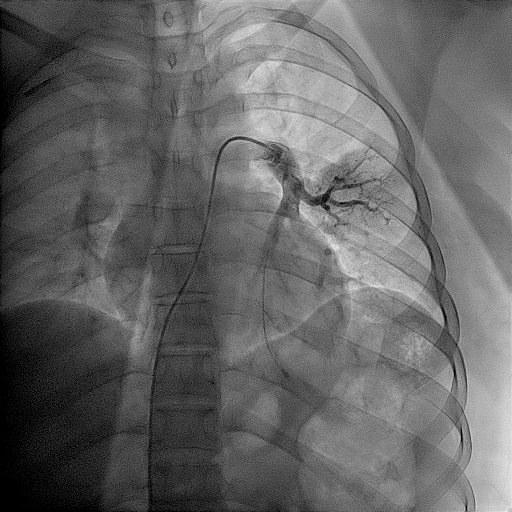

A twenty nine years old lady diagnosed as Carcinoma left breast underwent breast conservation surgery (pT2N2aM0, ER positive PR positive Her 2 neu positive) and presented for adjuvant chemotherapy. She was planned for adjuvant chemotherapy, radiotherapy and hormonal therapy as per standard guidelines. Chemoport reservoir was placed in the chest wall – right infraclavicular fossa and chemoport catheter was placed in the right subclavian vein. Post-procedure chest x ray revealed proper placement of the chemoport. She underwent first cycle of adjuvant chemotherapy with Docetaxel, Carboplatin and Trastuzumab without any complications. When she presented for second cycle (45 days after chemoport insertion), she was asymptomatic. However, there was no backflow of blood from the chemoport reservoir. Chest X ray revealed fragmentation and embolization of chemoport catheter. ECG showed normal sinus rhythm. Non Contrast CT scan chest was done, which revealed that the distal fragment of chemoport catheter had embolized to left pulmonary artery lower lobar branch, having migrated across the right atrium, right ventricle, main pulmonary artery and its left branch (Figure 1). After informed consent, retrieval of distal fragment of chemoport catheter was done in cath lab under local anesthesia under fluoroscopic guidance by Interventional Radiology team. It was retrieved from left pulmonary artery lower lobar branch in a procedure lasting forty minutes. The right femoral vein was punctured, 10 Fr Cordis sheath was introduced into the femoral vein, left pulmonary artery was cannulated using cobra 5 Fr catheter and then it was exchanged with snare over the guide wire. The left posterior inferior branch of pulmonary artery was selectively cannulated using Terumo guide wire and Cobra catheter. The tip of the foreign body was snared using Sequre snare system (4Fr, 10mm) and pulled through the pulmonary artery (Figure 2). The length of the catheter fragment was 4cm (Figure 3-9). The next day, chemoport reservoir and the proximal fragment of chemoport catheter was retrieved by surgery under local anesthesia. Patient tolerated both procedures well and was discharged on the third day.

Figure 4 Fluoroscopy image showing snare catheter in left pulmonary artery with foreign body in left pulmonary artery branch.

Figure 5 Fluoroscopy image showing snare catheter adjacent to the foreign body in left pulmonary artery branch.